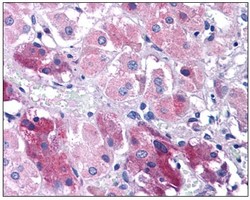

Supportive validation

- Submitted by

- OriGene (provider)

- Main image

- Experimental details

- Human Adrenal: Formalin-Fixed, Paraffin-Embedded (FFPE)

- Validation comment

- IHC